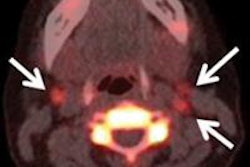

Whole-body FDG-PET/CT offers "excellent diagnostic performance" in the assessment of distant malignancies in patients with head and neck, breast, and lung cancers, according to a new study in the Journal of Nuclear Medicine.

A meta-analysis of 41 studies by Chinese researchers found that whole-body FDG-PET/CT achieved overall sensitivity of 93% and specificity of 96% in these forms of cancer. In cases of breast cancer, the hybrid modality achieved sensitivity of 97% and specificity of 95%, according to a research team led by Dr. Guozeng Xu of the Evidence-Based Medical Center and the First Affiliated Hospital of Guangxi Medical University in Nanning (JNM, December 2012, Vol. 53:12, pp. 1847-1854).